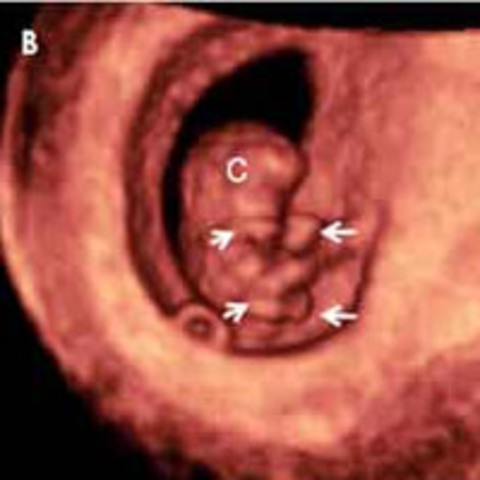

El embrión es un grupo de células que se están multiplicando muy rápidamente dentro del útero materno. Tras la fecundación del ovocito por el espermatozoide, se fusionan los dos núcleos aportando cada uno 23 cromosomas con la dotación genética de ambos.Tu hijo tendrá un total de 46 cromosomas con una información en ellos tuya y de tu pareja.

Desde el momento de la fecundación, ya está establecido el sexo del bebé, y éste viene determinado por el tipo de espermatozoide que fecunde el ovocito.

• Semana 4

Semana 4

Clave para confirmar tus sospechas de que esperas un bebé.

se produce unos de los hitos de la gestación: la implantación del embrión en la cavidad uterina. Y la naturaleza sigue su curso: la diferenciación de las células embrionarias en capas, que llegarán a desarrollar los diferentes órganos, y las primeras fases de la placenta. El embrión ya implantado en el útero materno tiene un tamaño de entre 0,36 a 1 milímetros de longitud.